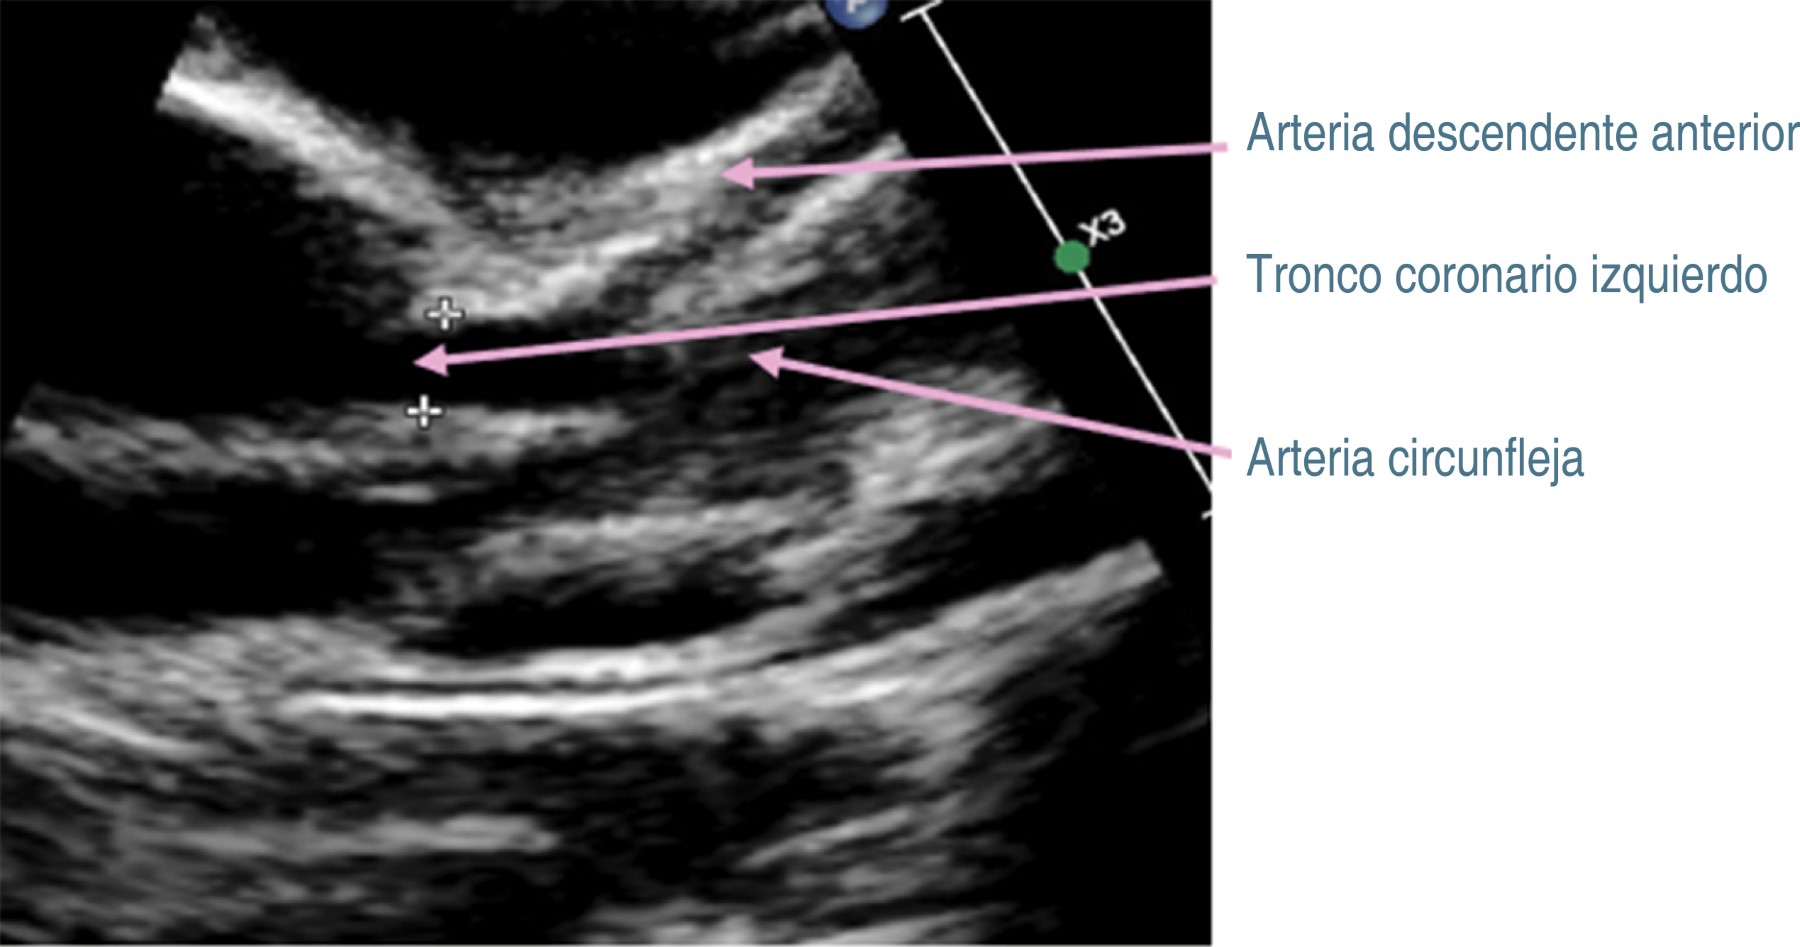

Tras 30 días del padecimiento y por la persistencia de la fiebre, se decide traslado a nuestro hospital. A su ingreso se corrobora fiebre, se ausculta soplo cardiaco holosistólico en mesocardio grado II/VI y soplo sistólico regurgitante en foco tricuspídeo grado II/VI, pero sin repercusión hemodinámica. Se decide continuar con antibióticos, iniciando protocolo de estudio de fiebre de origen a determinar. En nuevos exámenes de laboratorio (Tabla 1, columna B), se determina leucocitosis, neutrofilia, trombocitosis e hipoalbuminemia. Radiografía de tórax, ultrasonido abdominal y tomografía computarizada de cráneo fueron normales. En electrocardiograma se observó crecimiento de cavidades izquierdas, sospechando endocarditis, por lo que se realiza ecocardiograma transtorácico (ECT), con los siguientes hallazgos: persistencia de conducto arterioso; en arteria coronaria izquierda (Figura 1) se observa aneurisma sacular que mide 4.6 mm de ancho y 5.2 mm de longitud (z-score +9.2), así como imagen sugestiva de trombo en su interior. En coronaria derecha (Figura 2), origen: 4.2 mm (z-score +8.6), se observan dos aneurismas fusiformes en la porción proximal, uno mide 9.9 × 53.9 mm (z-score + 7.7), y otro más en la porción distal que mide 7.6 × 3.2 mm (z-score +7.1). Además, se detectó derrame pericárdico laminar y función sistólica ventricular conservada.

Los datos previos orientaron a que se trataba de EK, por lo que se inicia inmunoglobulina intravenosa (IGIV) humana a dosis de 2 g/kg/día, ácido acetilsalicílico (ASA) a dosis de 80 mg/kg/día, clopidogrel (0.5 mg/kg/día) y enoxaparina (1 mg/kg/dosis). La fiebre cede en las primeras 24 horas, presentando mejoría del estado general. Cinco días después, en ECT de control, el tronco coronario izquierdo medía 3.9 mm (z-score +7.05), sin evidencia de trombo en su interior. Mientras que en la coronaria derecha hay regresión de aneurismas fusiformes a aneurismas pequeños, midiendo 2.4 × 5.4 mm en porción proximal (z-score + 3.16), y de 1.9 × 4.5 mm en porción distal (z-score + 2.75) (Figura 3). En el tronco coronario izquierdo medía de 3.9 (z-score + 7.05), sin evidencia de trombo (Figura 4).

Figura 4